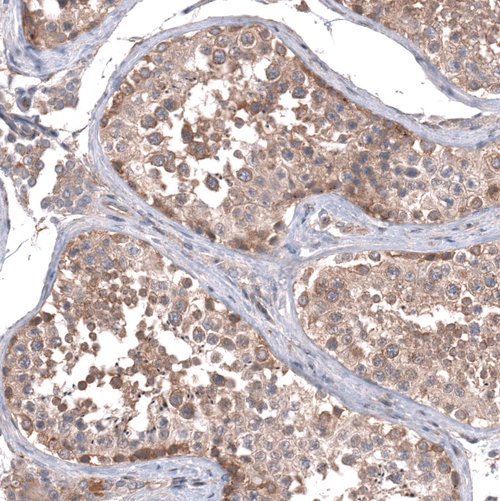

Immunohistochemical staining of human testis shows moderate cytoplasmic/cytoplasmic-membranous positivity in cells in seminiferous ducts.